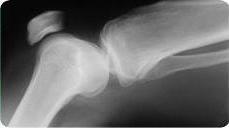

Ceļa locītavas problēmas

Ceļa locītava ir liela un svarīga locītava, kas nodrošina mums brīvu pārvietošanās iespēju. Ceļa stabilitāti nodrošina saites un meniski, kuri piedalās rotācijā un svara pārnešanā. Muskuļu spēks nodrošina ceļa un kājas kustību.

Jebkuras struktūras bojājums rada sāpes un samazina ceļa locītavas stabilitāti, kas veicina atkārtotu traumatismu. Neārstēta ceļa locītava rada papildus problēmas mugurā un gūžas locītavā.